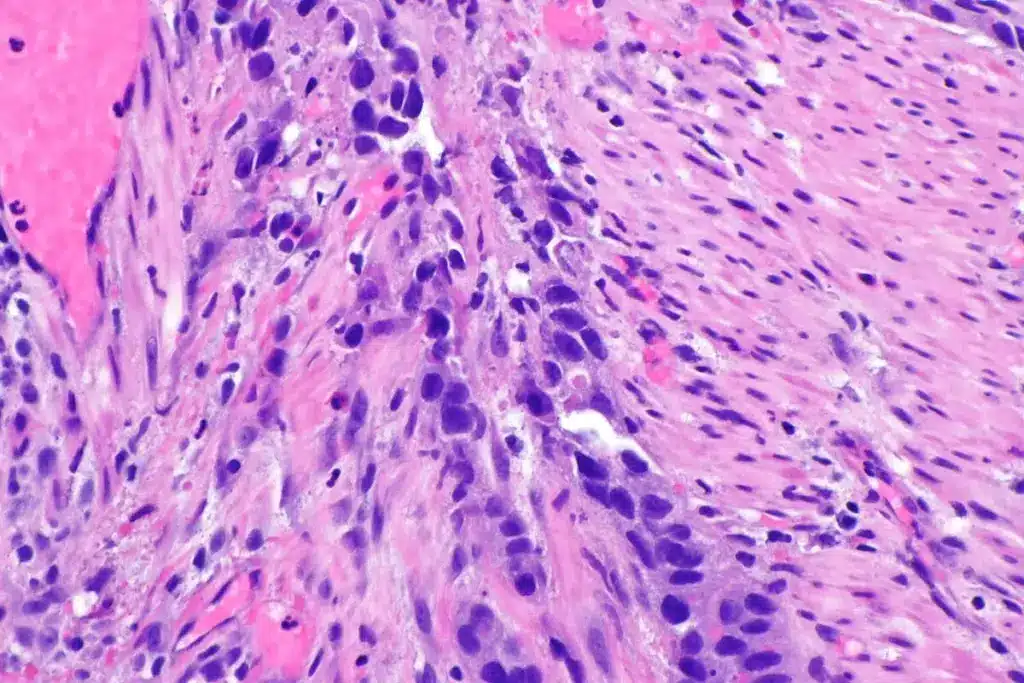

Understanding Transitional Cell Carcinoma

Transitional cell carcinoma (TCC), also known as urothelial carcinoma, is the most common type of bladder cancer, accounting for about 90% of all cases. It begins in the urothelial cells that line the inside of the bladder. TCC can be further divided into two subtypes: low-grade and high-grade, depending on how much the cancer cells resemble normal cells under a microscope.

Low-grade TCC tends to grow slowly and is less likely to invade the bladder muscle. In contrast, high-grade TCC grows more aggressively and is more likely to spread to other parts of the body. Understanding the grade of TCC is crucial for determining the prognosis and choosing the appropriate treatment.